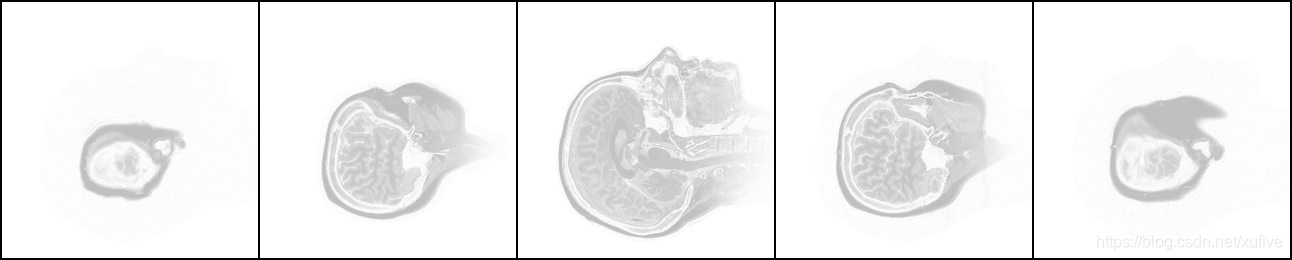

我手头这套头部CT断层扫描片共有109张,是侧卧位的水平断层扫描,从一侧开始至另一侧结束。下图从左至右分别是第11张、第21张、第55张、第89张、第99张。不难看出,中间的一张面积最大,是鼻梁正中的断层图片,鼻尖朝向图片上方,越往两侧的图片,面积越小。